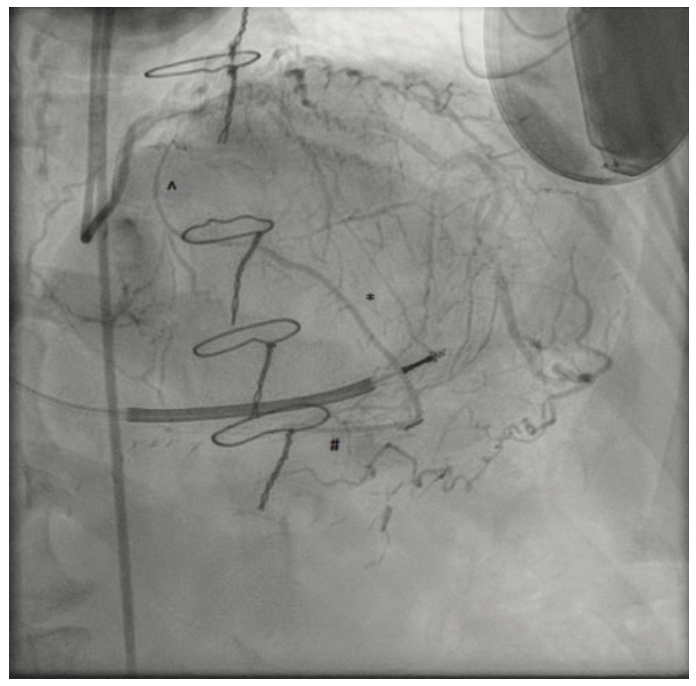

The ipsilateral collaterals to the culprit vessel precluded the need for dual access, and a 6 French (F) VL3 guide catheter (Boston Scientific) was placed via the right femoral access. A Turnpike LP microcatheter (Teleflex) was used for wire support and exchanges. Initial crossing attempts with Runthrough NS Extra Floppy (Terumo Interventional Systems) and Fielder XT-a (Asahi Intecc) wires were unsuccessful. The lesion was crossed successfully with a MiracleBros 6 (Asahi Intecc) wire and the tip was clearly visualized in the remains of the jump graft (Figure 4). Attempts to then cross the lesion with Turnpike LP and Turnpike Gold microcatheters (Teleflex) for lesion dilation and possible wire exchange were unsuccessful despite very good guide support (Figure 5).